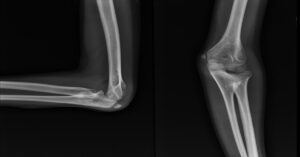

Önkol kemiklerinin dirsek eklemindeki ayrılarak yer değiştirmesiyle oluşur. Dirsek; üst kolda bulunan humerus ile ön koldaki radius ve ulna kemiklerinden oluşur. Bu üç kemiğin uyum içinde hareket etmesini sağlayan güçlü bağlar, kapsül yapıları ve kaslar bulunur. Travma sonucu bu uyum bozulduğunda eklem bütünlüğü kaybolur ve çıkık meydana gelir. Bu noktada birçok kişi dirsek çıkığı nedir? sorusunu merak eder, çünkü yaralanma anında ortaya çıkan ağrı, şişlik ve şekil bozukluğu oldukça belirgindir.

Dirsek eklemini oluşturan kemiklerin doğal hizasından ayrılmasıyla oluşan bir yaralanmadır. Dirsek, günlük hayatta sık kullanılan bir eklemdir. Bu nedenle düşme veya ani bir darbe sonrası kolayca zarar görebilir.